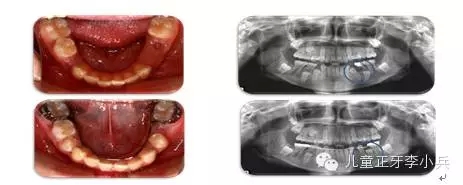

2. 彎根牙的早期牽引助萌:先天及乳牙外傷導(dǎo)致繼承恒牙牙冠及牙根發(fā)育異常,臨床出現(xiàn)牙冠發(fā)育不全及彎根牙。彎根牙的牽引助萌常受到彎根嚴(yán)重程度及彎根角度的影響,早期牽引能引導(dǎo)牙根形成方向,降低牙根彎曲的嚴(yán)重程度。(圖3,彎根牙的早期牽引治療)

圖 3 11彎根牙的早期牽引,11牙根繼續(xù)發(fā)育,牙根彎曲程度減小;